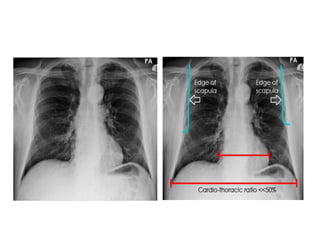

 Size measurement:

• CT ratio: < 50%

• Transverse cardiac

diameter:

< 15.5 cm (M)

< 14.5 cm (F)

 Good centering:

– Heart:

• 2/3 left

• 1/3 right